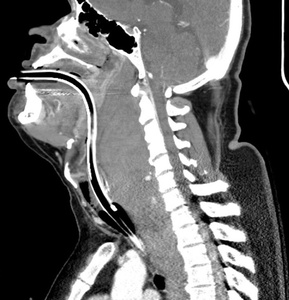

The American Society of Anesthesiologists (ASA) recommends awake intubation in cases with airways with suspected difficult intubation, ventilation, or desaturation risk5 (Figure 3). While awake fiber-optic intubation is often preferred, it was deferred in this case given its limited capacity for suctioning large volumes through its small aspiration port.6 Studies suggest that sedation can diminish voluntary efforts to maintain airway patency, potentially increasing the risk of progression from partial to complete obstruction.7 To mitigate this risk in our case, we utilized IV ketamine alone for induction, allowing the patient to maintain spontaneous breathing before intubation.